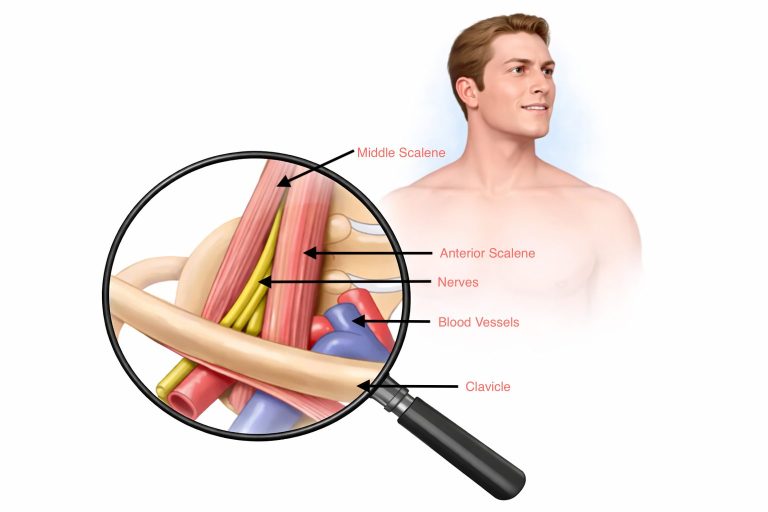

The “thoracic outlet” is not one single tunnel; it is a region where the brachial plexus (nerves to the arm) and the subclavian vessels (artery and vein) pass between the neck, collarbone, first rib, and chest wall on the way into the arm. Compression can occur in more than one place, and it can be positional (worse with lifting the arm, overhead work, or sustained posture).

For patient education, it is usually easiest to think in terms of three common compression spaces:

1) Interscalene triangle (between the anterior and middle scalene muscles): mainly affects the brachial plexus and subclavian artery.

2) Costoclavicular space (between the collarbone and first rib): can affect nerves and blood vessels, particularly with posture (shoulders drooping forward) or load (bags/straps).

3) Subcoracoid / retro-pectoralis minor space (under the pectoralis minor near the coracoid): may contribute to symptoms, especially with shoulder protraction and overhead use.